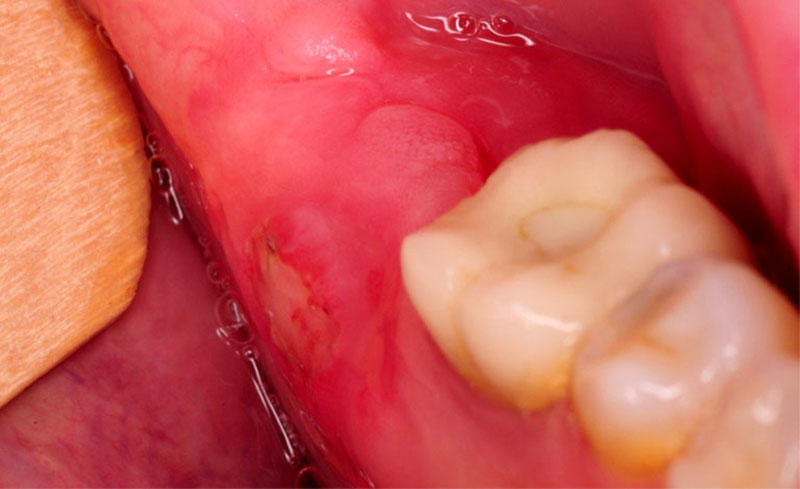

Hình ảnh giới thiệu về Viêm lợi trùm

Viêm lợi trùm là một bệnh lý liên quan đến quá trình phát triển của răng khôn. Phần lợi trên mặt răng khôn sẽ gây cản trở khiến răng khôn không thể mọc lên.

Phần răng khôn lúc đó sẽ tiếp tục mọc và đâm vào phần lợi, gây ra cảm giác khó chịu cho người bệnh.

Trong quá trình mọc răng khôn, thường bệnh nhân sẽ phải đối mặt nhiều lần với tình trạng viêm lợi trùm nặng, phần lợi trùm bị sưng phồng gây đau đớn trong quá trình ăn uống.

Nếu không có vi khuẩn tấn công, thông thường lợi sẽ tự phục hồi sau 3-4 ngày. Tuy nhiên, một số trường hợp, phần lợi trùm bị viêm có thể gây đau đớn kéo dài cho người bệnh, thậm chí có thể khiến phát sốt. Vậy nên, trong trường hợp này, cần tới nha sĩ để được tư vấn và khám chữa kịp thời.